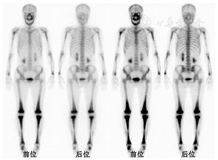

本例是以骨骼多发病变为主的病例,外院已行病变活组织检查(简称活检)并且有了较为明确的病理诊断,考虑为ECD。所以我们要考虑的问题就是,这个病例的骨显像以及其他临床特点是否符合ECD表现?ECD属于组织细胞增生症,与朗格汉斯组织细胞增生症(Langerhans cell histiocytosis, LCH)不同,ECD是非朗格汉斯组织细胞疾病,可能来源于单核巨噬细胞系。ECD可累及全身多个系统,最常受累的是骨骼系统,占95%;几乎所有ECD骨受累的图像都表现为以四肢长骨骨干为主的、对称性的骨质硬化和成骨性病灶,大多累及干骺端,并且以下肢更为多见,其次也可累及颅骨(颌面骨为著),脊柱和骨盆骨也可受累[1]。骨显像上ECD最典型的表现为双侧股骨远端、胫骨近端及胫骨远端弥漫性、对称性摄取增高(图3)。本例患者骨骼病变以中轴骨为主,并且病变大多伴明显的溶骨性破坏,和ECD的骨病特点不相符。其次,ECD一般是多系统受累,很少出现单系统病变,除骨骼系统外,心血管系统、肺、肾周、中枢神经系统(眼眶、垂体为主)、皮肤等亦是ECD常累及的部位,而本例患者在外院行18F-FDG PET/CT显像,临床和影像都没有发现骨骼系统以外的病变证据。ECD患者的症状一般与累及的系统有关,如可出现骨痛、胸闷、突眼、尿崩等症状,患者病程中很少出现发热,并且ECD好发于中老年人,本例患者的年龄、发热病程亦不典型。ECD的治疗首选为干扰素,有时会辅助糖皮质激素,但本例患者在经干扰素和糖皮质激素治疗后症状却逐渐加重。综上,本例无论是骨骼病变的影像特点还是临床特点,都不支持ECD的诊断。